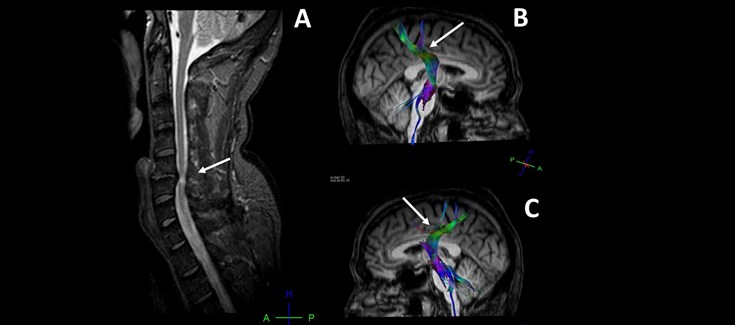

Los investigadores han aplicado herramientas y técnicas de neuroimagen médica avanzadas para tratar de entender mejor lo que sucede en el cerebro de pacientes crónicos con lesiones compresivas por hernias cervicales. Estas técnicas han permitido estudiar tanto la corteza cerebral como las fibras nerviosas de sustancia blanca y los patrones de conexión entre las distintas áreas cerebrales, lo que permite detectar cambios patológicos no observables en los estudios de resonancia magnética convencionales.

“Hemos demostrado que existen cambios a nivel cerebral y en las vías de comunicación de las señales cerebrales que se manifiestan sobre todo por atrofia cortical y daños en la corteza sensorial y motora” explica Eduardo Fernández Jover, coautor de la publicación y director del Grupo de Neuroingeniería Biomédica de la UMH y del CIBER-BBN. “Estos cambios se desconocían hasta ahora y pueden ayudar a comprender mejor la evolución clínica de muchos pacientes y abrir nuevas vías de diagnóstico y tratamiento de esta patología tan frecuente” añade.